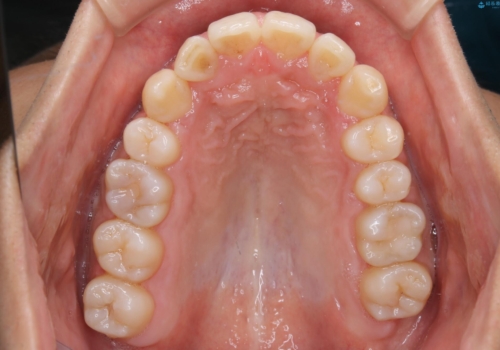

一見、表面はそこまで汚れが付着していないようにみえますが、裏面を見てみると、着色や歯石が多く付着していました。個人差はありますが、3カ月に1回の来院でもここまで汚れが付着する為、メンテナンスやクリーニングは、3ヶ月に1回をおすすめします。